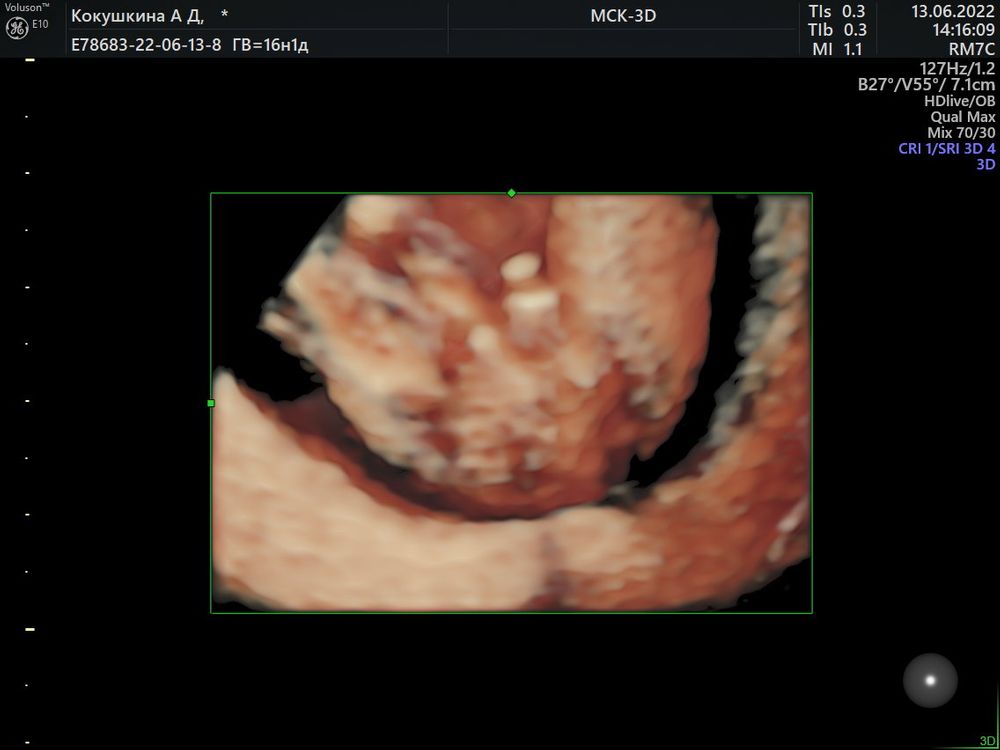

Узнали пол малыша в 16-17 недель🥰

На первом и правда не видно половой бугорок.

Поздравляюююю😍😍😍🌸🌸🌸 это уже 3 пост, где пишут, что по первому скринингу возможно девочка, по второму уже точно мальчик😂 у меня тоже так получилось🤗🤗🤗